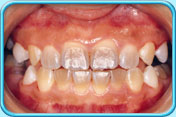

有橙色漬的牙齒牙齒沒給清潔乾淨,積聚在表面的牙菌膜含有一些能發出顏色的細菌或真菌,形成綠色或橙色的漬。

清除橙色漬後的牙齒每天早晚刷牙和使用牙線徹底清除牙菌膜,以保持牙齒潔白。